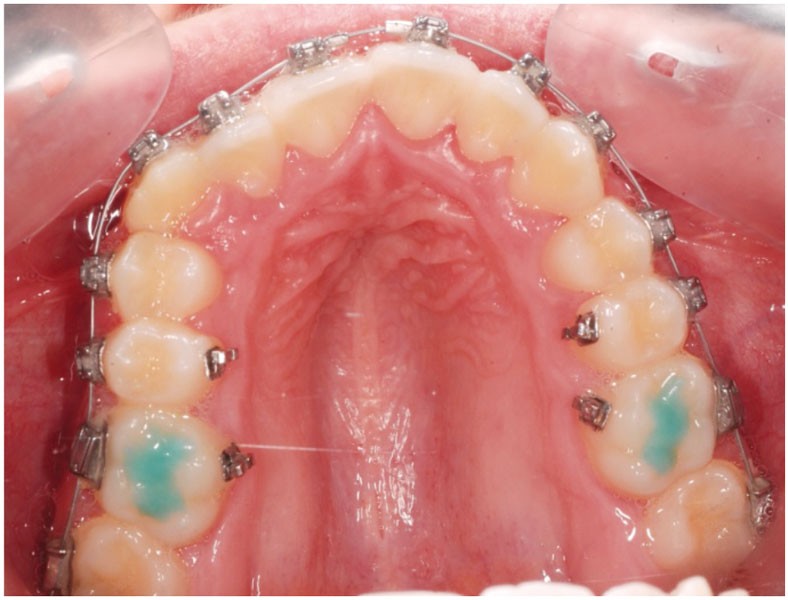

Sans aucun appareillage d’expansion, le maxillaire a été transformé et semble avoir été soumis à une disjonction (fig. 30).

Les moulages avant-après montrent une augmentation du sens transversal de 10 mm au niveau des 1re et 2e prémolaires (fig. 31).